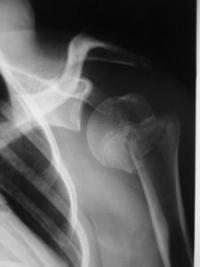

Exemples de décollements épiphysaires Salter 2